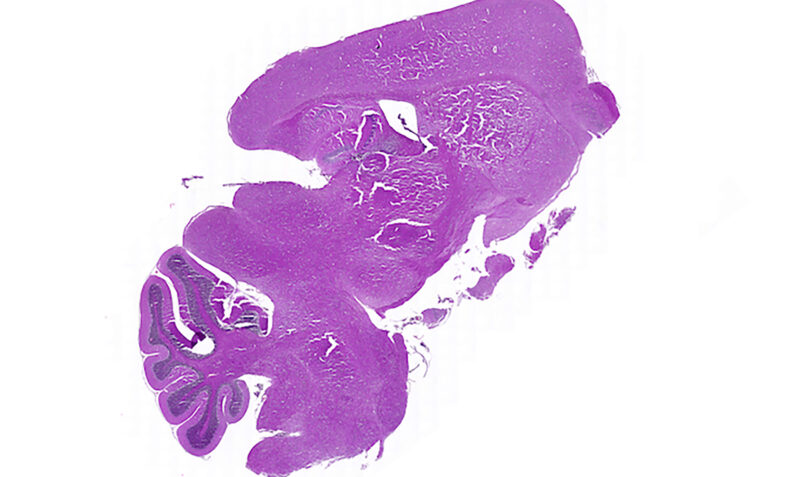

Purple tissue sample under microscope

A histological image of a tissue sample studied in the research, which found the CART T cells persisted in the preclinical models post treatment, acting as a ‘living drug’ to fight the tumour if it returns. Credit: WEHI researchers